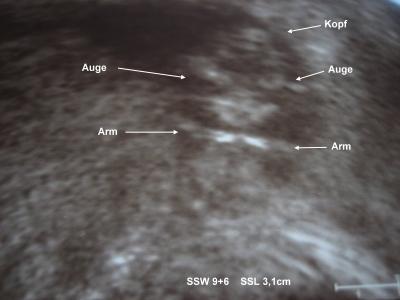

Hallo ihr Lieben, Muckelchen ist schon 3,1 cm gross, bin einen Tag hochgestuft worden - da ich genau weiss, wann unser Baby gezeugt wurde, stimmt es nun auf den Tag genau ;-) Es hat ganz doll gezappelt und hatte beide Ärmchen einmal kurz so, als wenn es Hanteln stemmen wollte - zauberhaft! Und sogar das Herzchen konnten wir schlagen hören - ganz kräftig! Wahnsinn, wie weit die Technik schon ist!!! Mein Mann und ich waren total hin und weg! Jetzt gehts mir erstmal wieder gut. Wir sollen uns nun Gedanken machen, ob wir eine Fruchtwasseruntersuchung machen lassen und/ oder die Nackenfaltenmessung.....mein Mann würde gern die Fruchtwasseruntersuchung machen lassen....ich hab da total Schiss vor....wir müssen uns das noch gut überlegen....

Bild zu War heute beim FA - Forum für November - Mamis

Da freu ich mich aber für Dich, das gibt einem doch gleich einen ganzen Glückschub an Hormonen. Ein süsses US-Bild, das hättest Du aber nicht extra beschriften brauchen, kann alles einwandfrei sehen Sonji